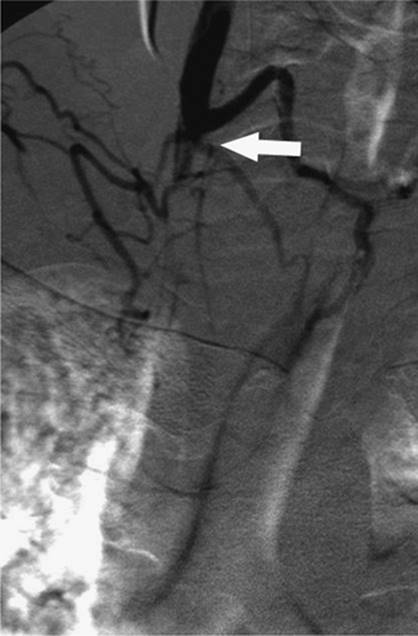

000431

Figure 35.14. Failed endoscopic placement of common bile duct (CBD) stent due to the presence of a large mass (black arrow) within the CBD. (Image courtesy of James Caridi, MD.)

000434

Figure 35.15. Successful percutaneous drainage using a left-sided biliary duct. Note that the drainage catheter has been advanced past the obstruction and into the small intestine. (Image courtesy of James Caridi, MD.)

000439

Figure 35.16. Patient presents with biliary obstruction. On hospital day 1, external drainage has been achieved using a right-sided bile duct approach. Cholangiogram shows complete obstruction in the mid common bile duct (CBD) (black arrow).

The indications for percutaneous biliary drainage include palliation of an unresectable primary or secondary malignancy of the liver causing biliary obstruction, benign strictures including biliary-enteric anastomosis as seen in liver transplant patients, sepsis secondary to biliary obstruction, preoperative decompression, stone removal, bile leak after laparoscopic cholecystectomy, biopsies, permanent internalization of drainage by placement of internal stent, and radiation therapy (29) (Figs. 35.18 and 35.19).

The only true contraindication to percutaneous biliary drainage is a bleeding diathesis. Usually this problem is overcome with the administration of blood products in the form of fresh frozen plasma, platelets, and vitamin K. Relative contraindications include the presence of sepsis, unless it is of biliary origin. The presence of ascites increases the risk of bleeding, and catheter misplacement, as well as making the procedure technically more difficult; hence ascitic fluid should be drained prior to performing the procedure. The presence of multiple intrahepatic obstructions also raises the risk of introducing bacteria to a bile duct that is not drained and that can rapidly become infected.

000443

Figure 35.17. On hospital day 2, internal/external drainage has been achieved by gaining access to the small intestine across the area of obstruction.

000250

Figure 35.18. This is the same patient as in Figures 35.16 and 35.17. A metallic self-expanding stent has been placed across the area of obstruction in the distal common bile duct. Note the waist in the stent (black arrow) due to the surrounding mass.

000446

Figure 35.19. Post–stent placement and balloon angioplasty. No residual stenosis is noted, and the stent is fully expanded.